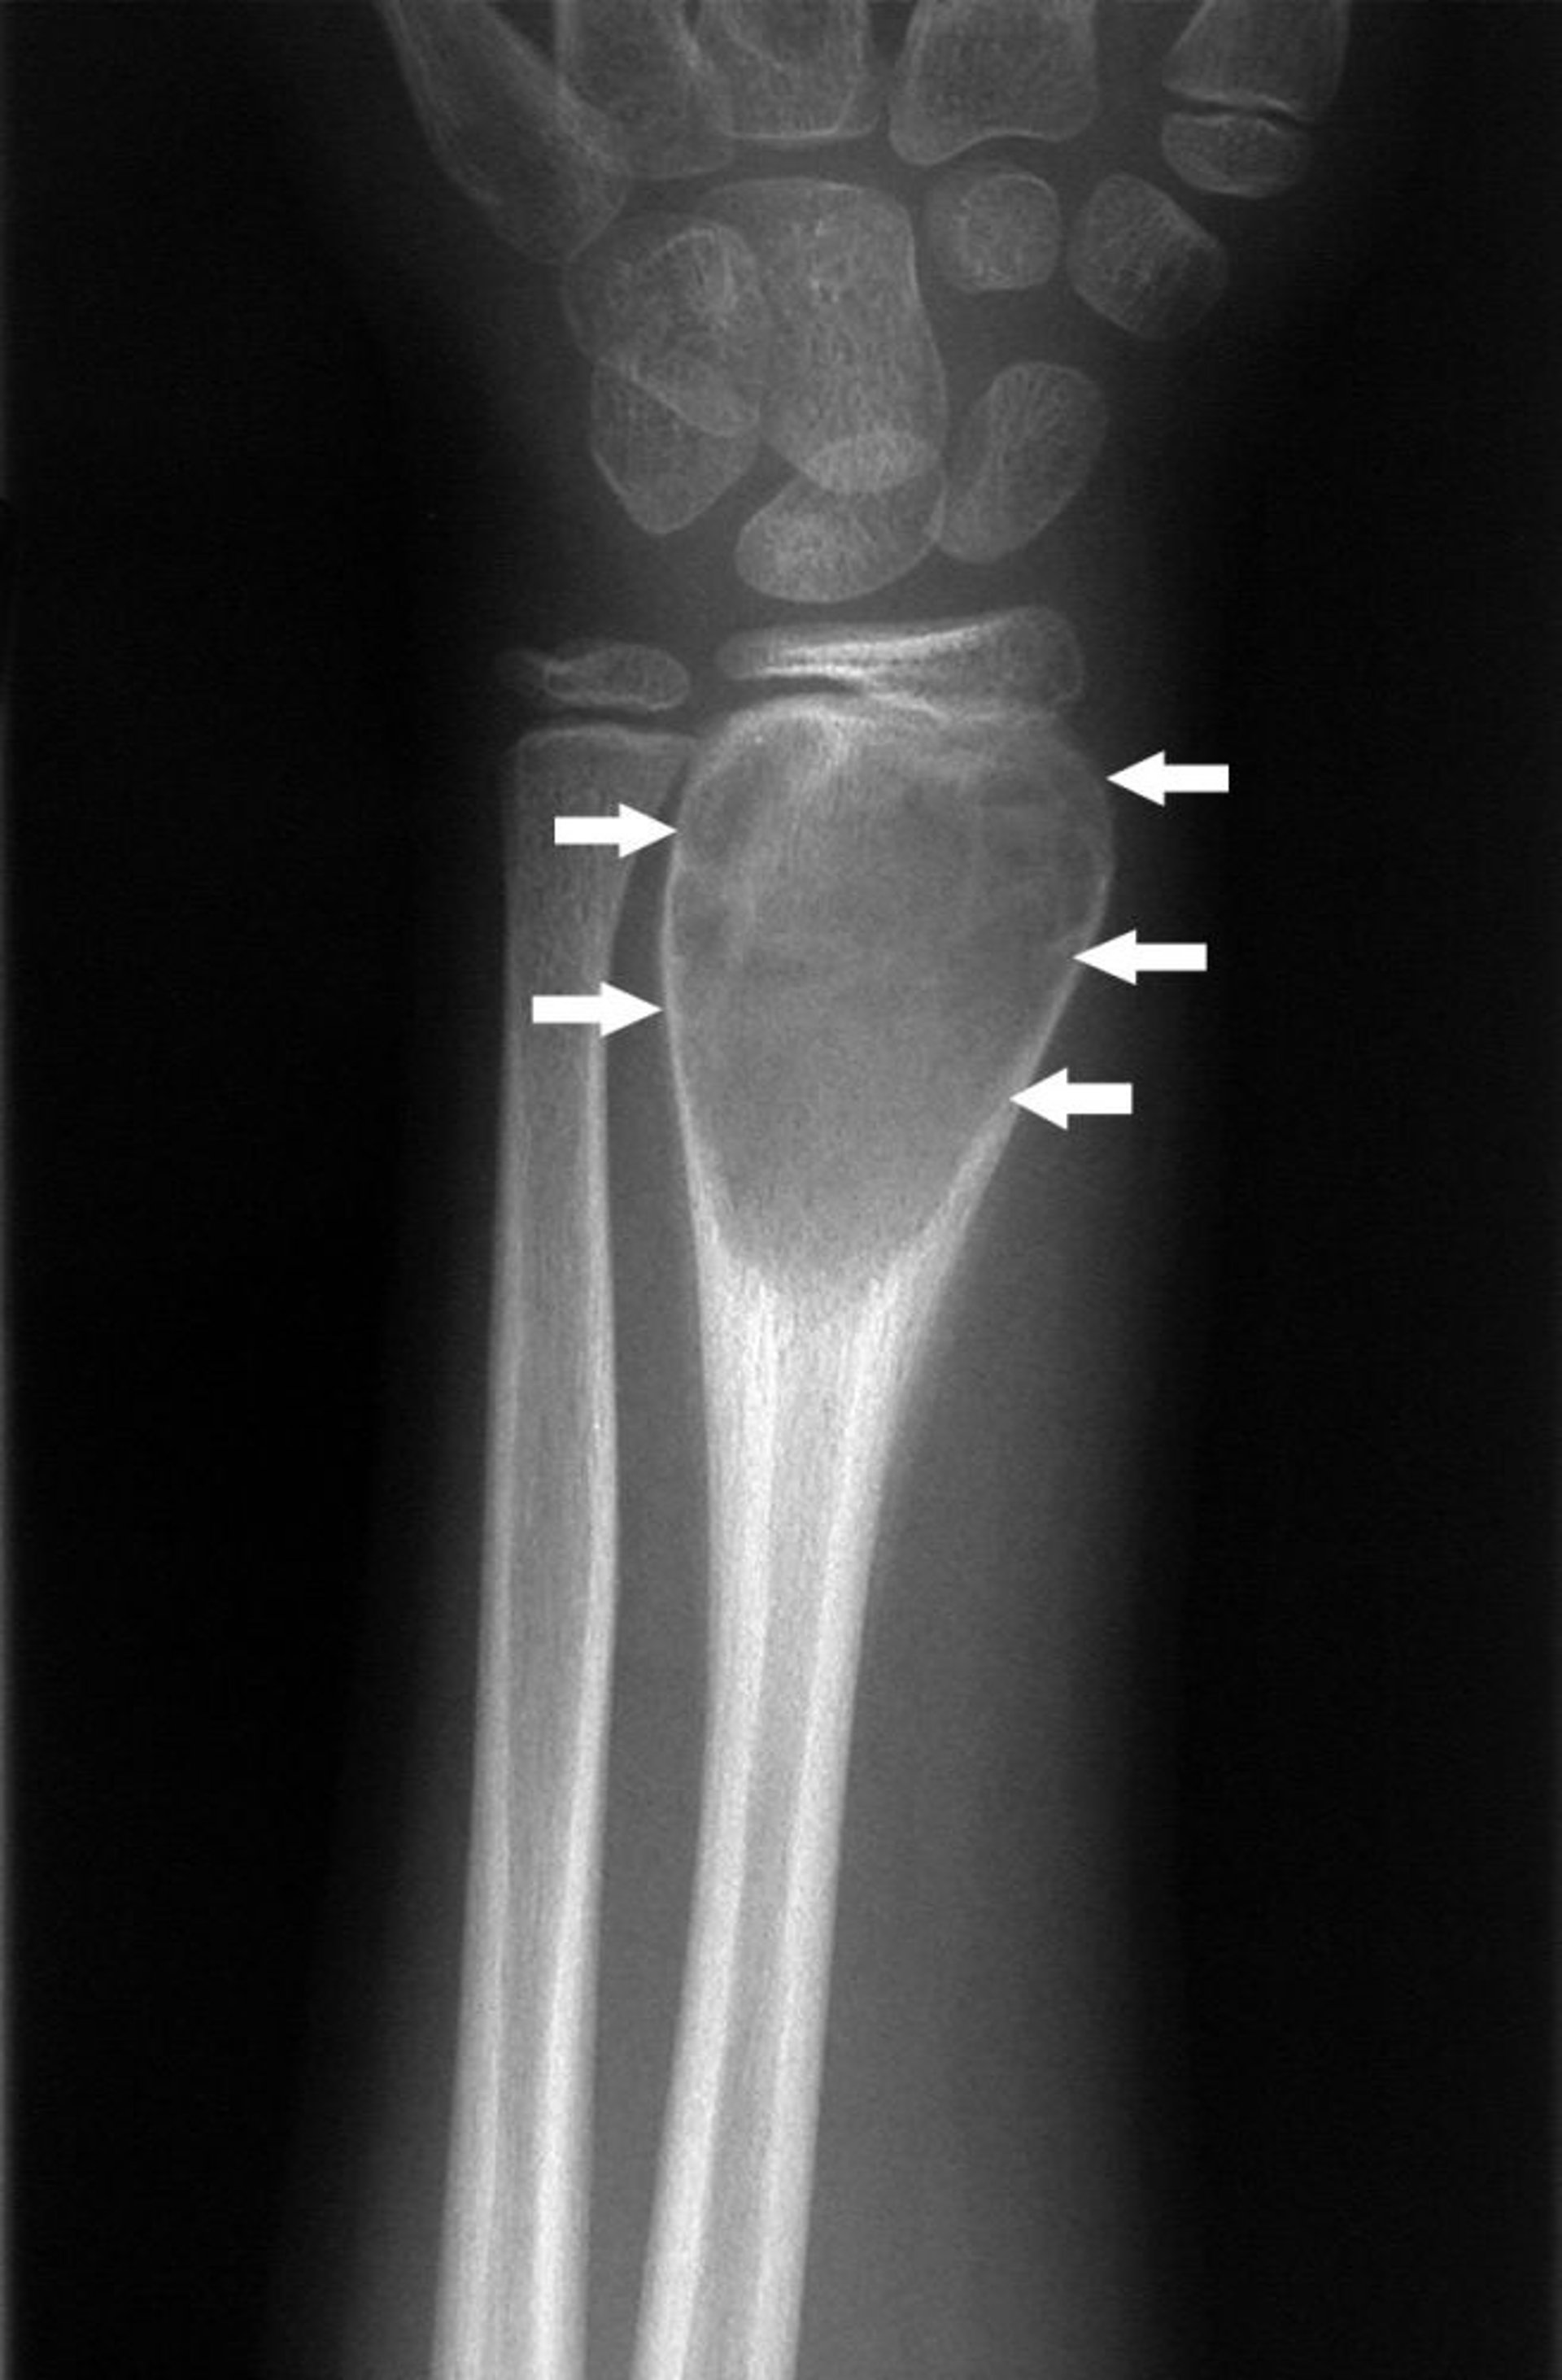

Quiste óseo aneurismático de la muñeca

Esta radiografía de la muñeca muestra un quiste óseo aneurismático (flechas).

Imagen cortesía de Michael J. Joyce, MD, y Hakan Ilaslan, MD.